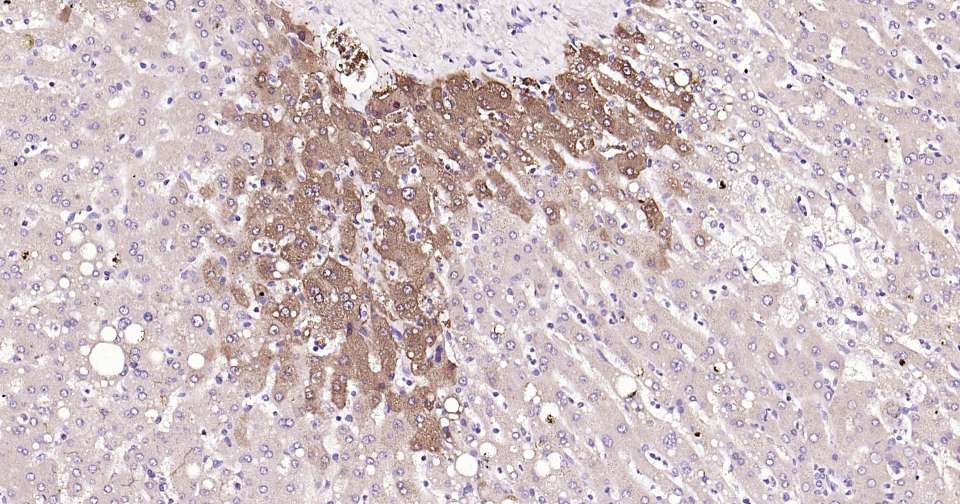

Immunohistochemical analysis of paraffin embedded mouse liver tissue slide using IHC0333 (Glutamine synthetase Kit).